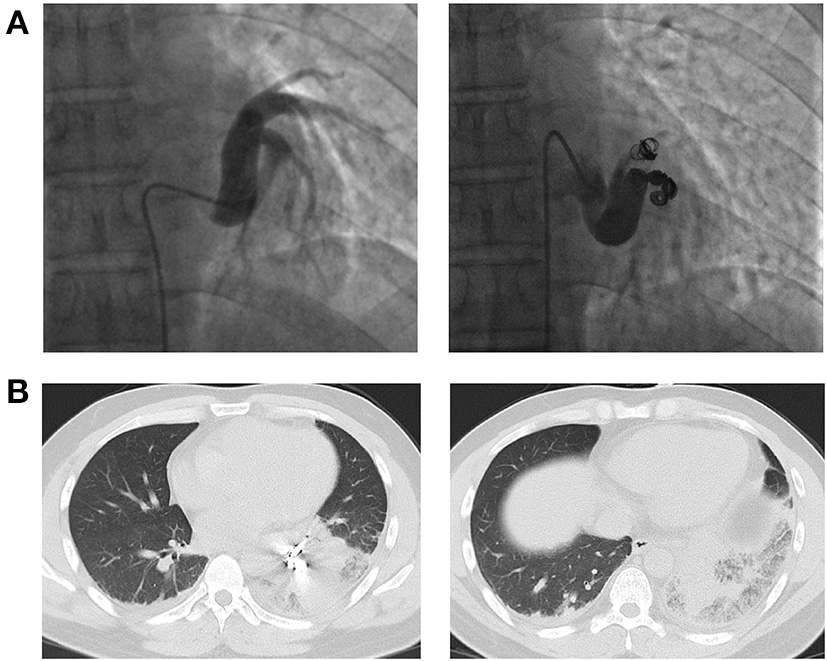

After multidisciplinary treatment (MDT) by thoracic surgery, vascular surgery and interventional radiology, we decided to perform interventional therapy via coil embolization to preserve as much lung tissue as possible and protect pulmonary function and obtained the patient's consent. The procedure was uneventful (Figure 2A). However, after 24 h, the patient developed severe chest pain accompanied by labored breathing (a clinical manifestation of pulmonary infarction), and levels of serum fibrinogen and D-dimer were elevated. Forty-eight hours after the intervention, chest CT showed signs of infarction of the left lower lobe (Figure 2B). Serious symptoms of pulmonary infarction were observed at 72–96 h after the intervention and were accompanied by fever. Morphine was given for analgesia and sedation. His symptoms gradually resolved at 1 week after the intervention, and the patient was discharged at 2 weeks after the intervention.

Figure 2

(A) Angiography and coil embolization for the anomalous systemic artery. (B) CT images showing pulmonary infarction at 48 h after the intervention.